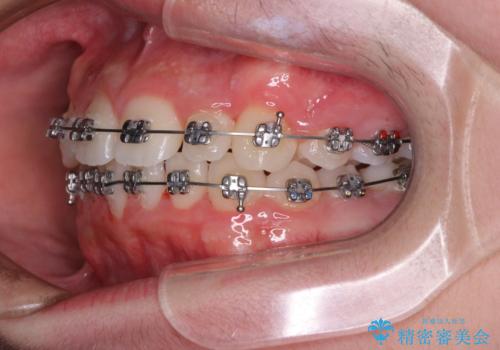

中学生のワイヤー矯正 クロスバイトを短期間で改善

- メタルブラケット

- 前歯のクロスバイトを気にして来院された患者様です。

中学生であることから、治療期間を短縮できると判断し、ワイヤー矯正にて短期間で治療を行うこととしました。

叢生のため磨き残しの多い歯列でしたが、1年弱で治療を終了でき、磨き残しや歯肉の腫れが著しく改善されました。